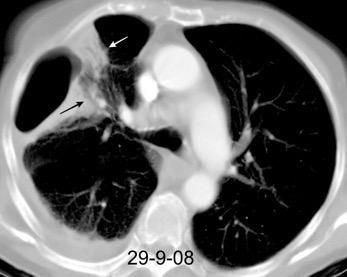

Marzo 2014: Perforación longitudinal distal secundaria a episodio de vómito (síndrome de Boerhaave). Derrame pleural izdo. que evoluciona a empiema.

Wang C-T et al. Tension hydropneumothorax in a Boerhaave syndrome patient: A case report . World J Emerg Med, 2021. Katabathina V et al. Nonvascular, nontraumatic mediastinal emergencies in adults:a comprehensive review of imaging findings. Radiographics. 2011.